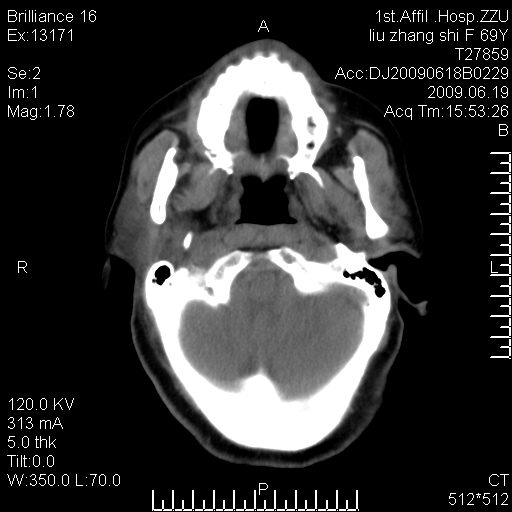

标题: CT26782:女,69岁,颈部占位,3天后公布病理结果。

【病理证实系列】女,69岁,颈部占位,有病理结果,3天后公布。(由于病例时间较久,临床资料不全,请网友见谅)本系列将有几百种常见、少见及罕见病例,均经病理证实。病例资料来自郑州大学第一附属医院。与网友共享,本人有空就发。

病理结果:颈部非霍奇金淋巴瘤。